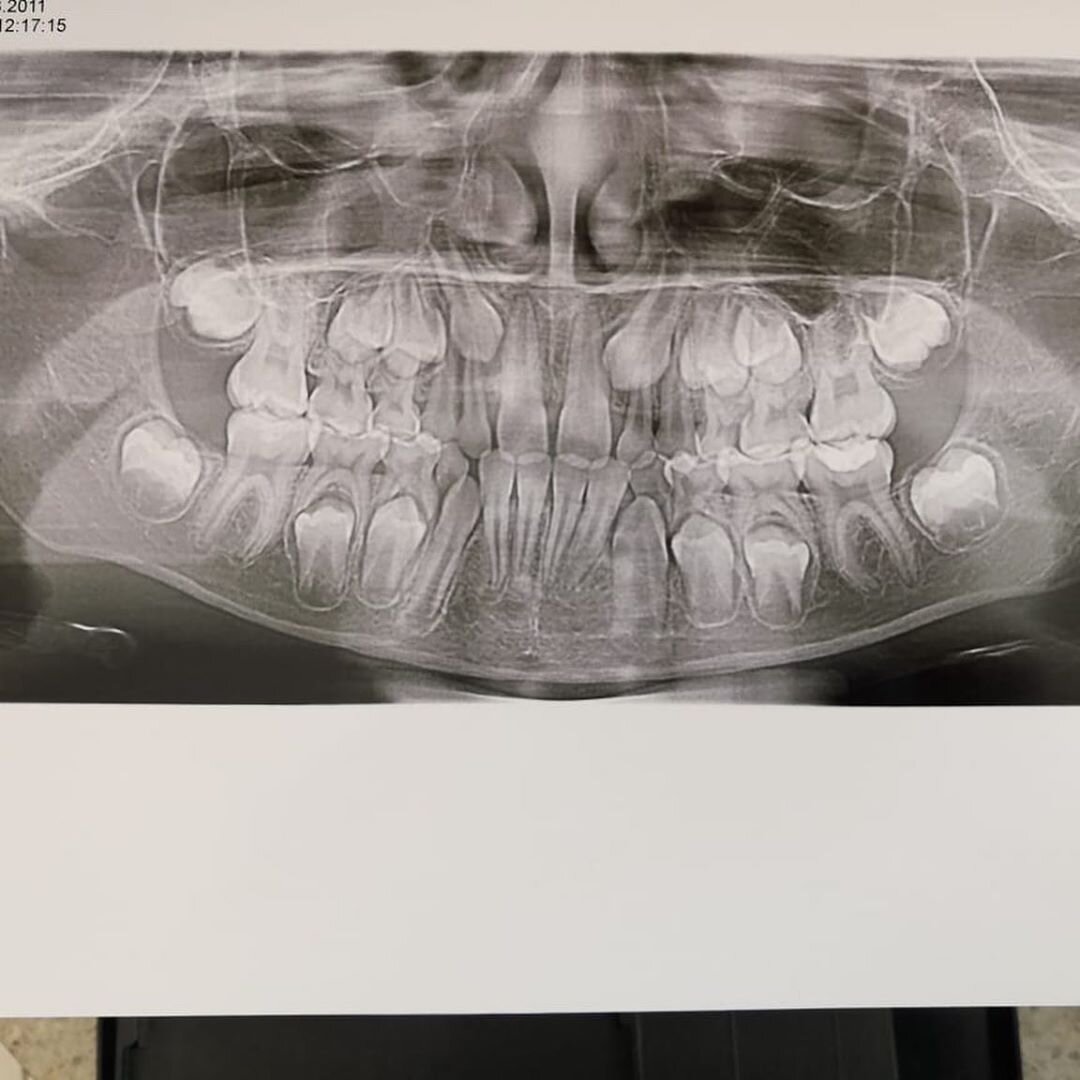

🦷Панорамный снимок детям

Наука не дает точного ответа, почему у одних людей зубы вырастают ровными и красивыми, а у других - кривыми. Это зависит от множества факторов. Чтобы вовремя заметить проблему, необходимо видеть корни и зачатки зубов. Легко решает эту задачу панорамный снимок зубов.

❗Обязательно необходимо сделать панорамный снимок каждому ребенку до пяти лет. Затем врачи рекомендуют делать его ежегодно, чтобы вовремя увидеть и устранить любую проблему.